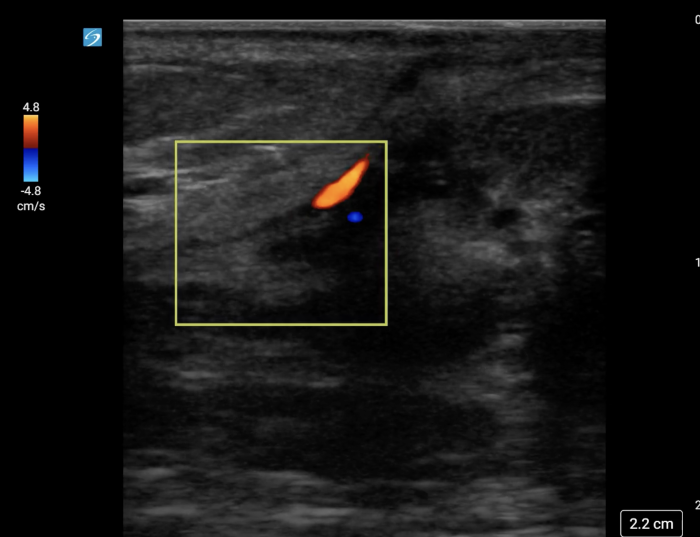

Image 4. Linear, untwisted appearance of the spermatic cord with accompanying vessels.

In your first image (Image 1), you realize there is no flow with color Doppler. Additionally, you find a torsed cord complex (Image 2), also known as the “corkscrew sign.” You consult Urology who is busy in the operating room with another case. You decide to perform a manual detorsion due to your concern for testicular atrophy and risk of infertility. Using the open book technique, you get relief of pain and return of vertical positioning of the testicle after two rotations. On your repeat testicular POCUS with color Doppler you obtain these images (Images 3 and 4), which demonstrate venous and arterial flow throughout the testicle. The cord is now untwisted and appears linear in orientation.